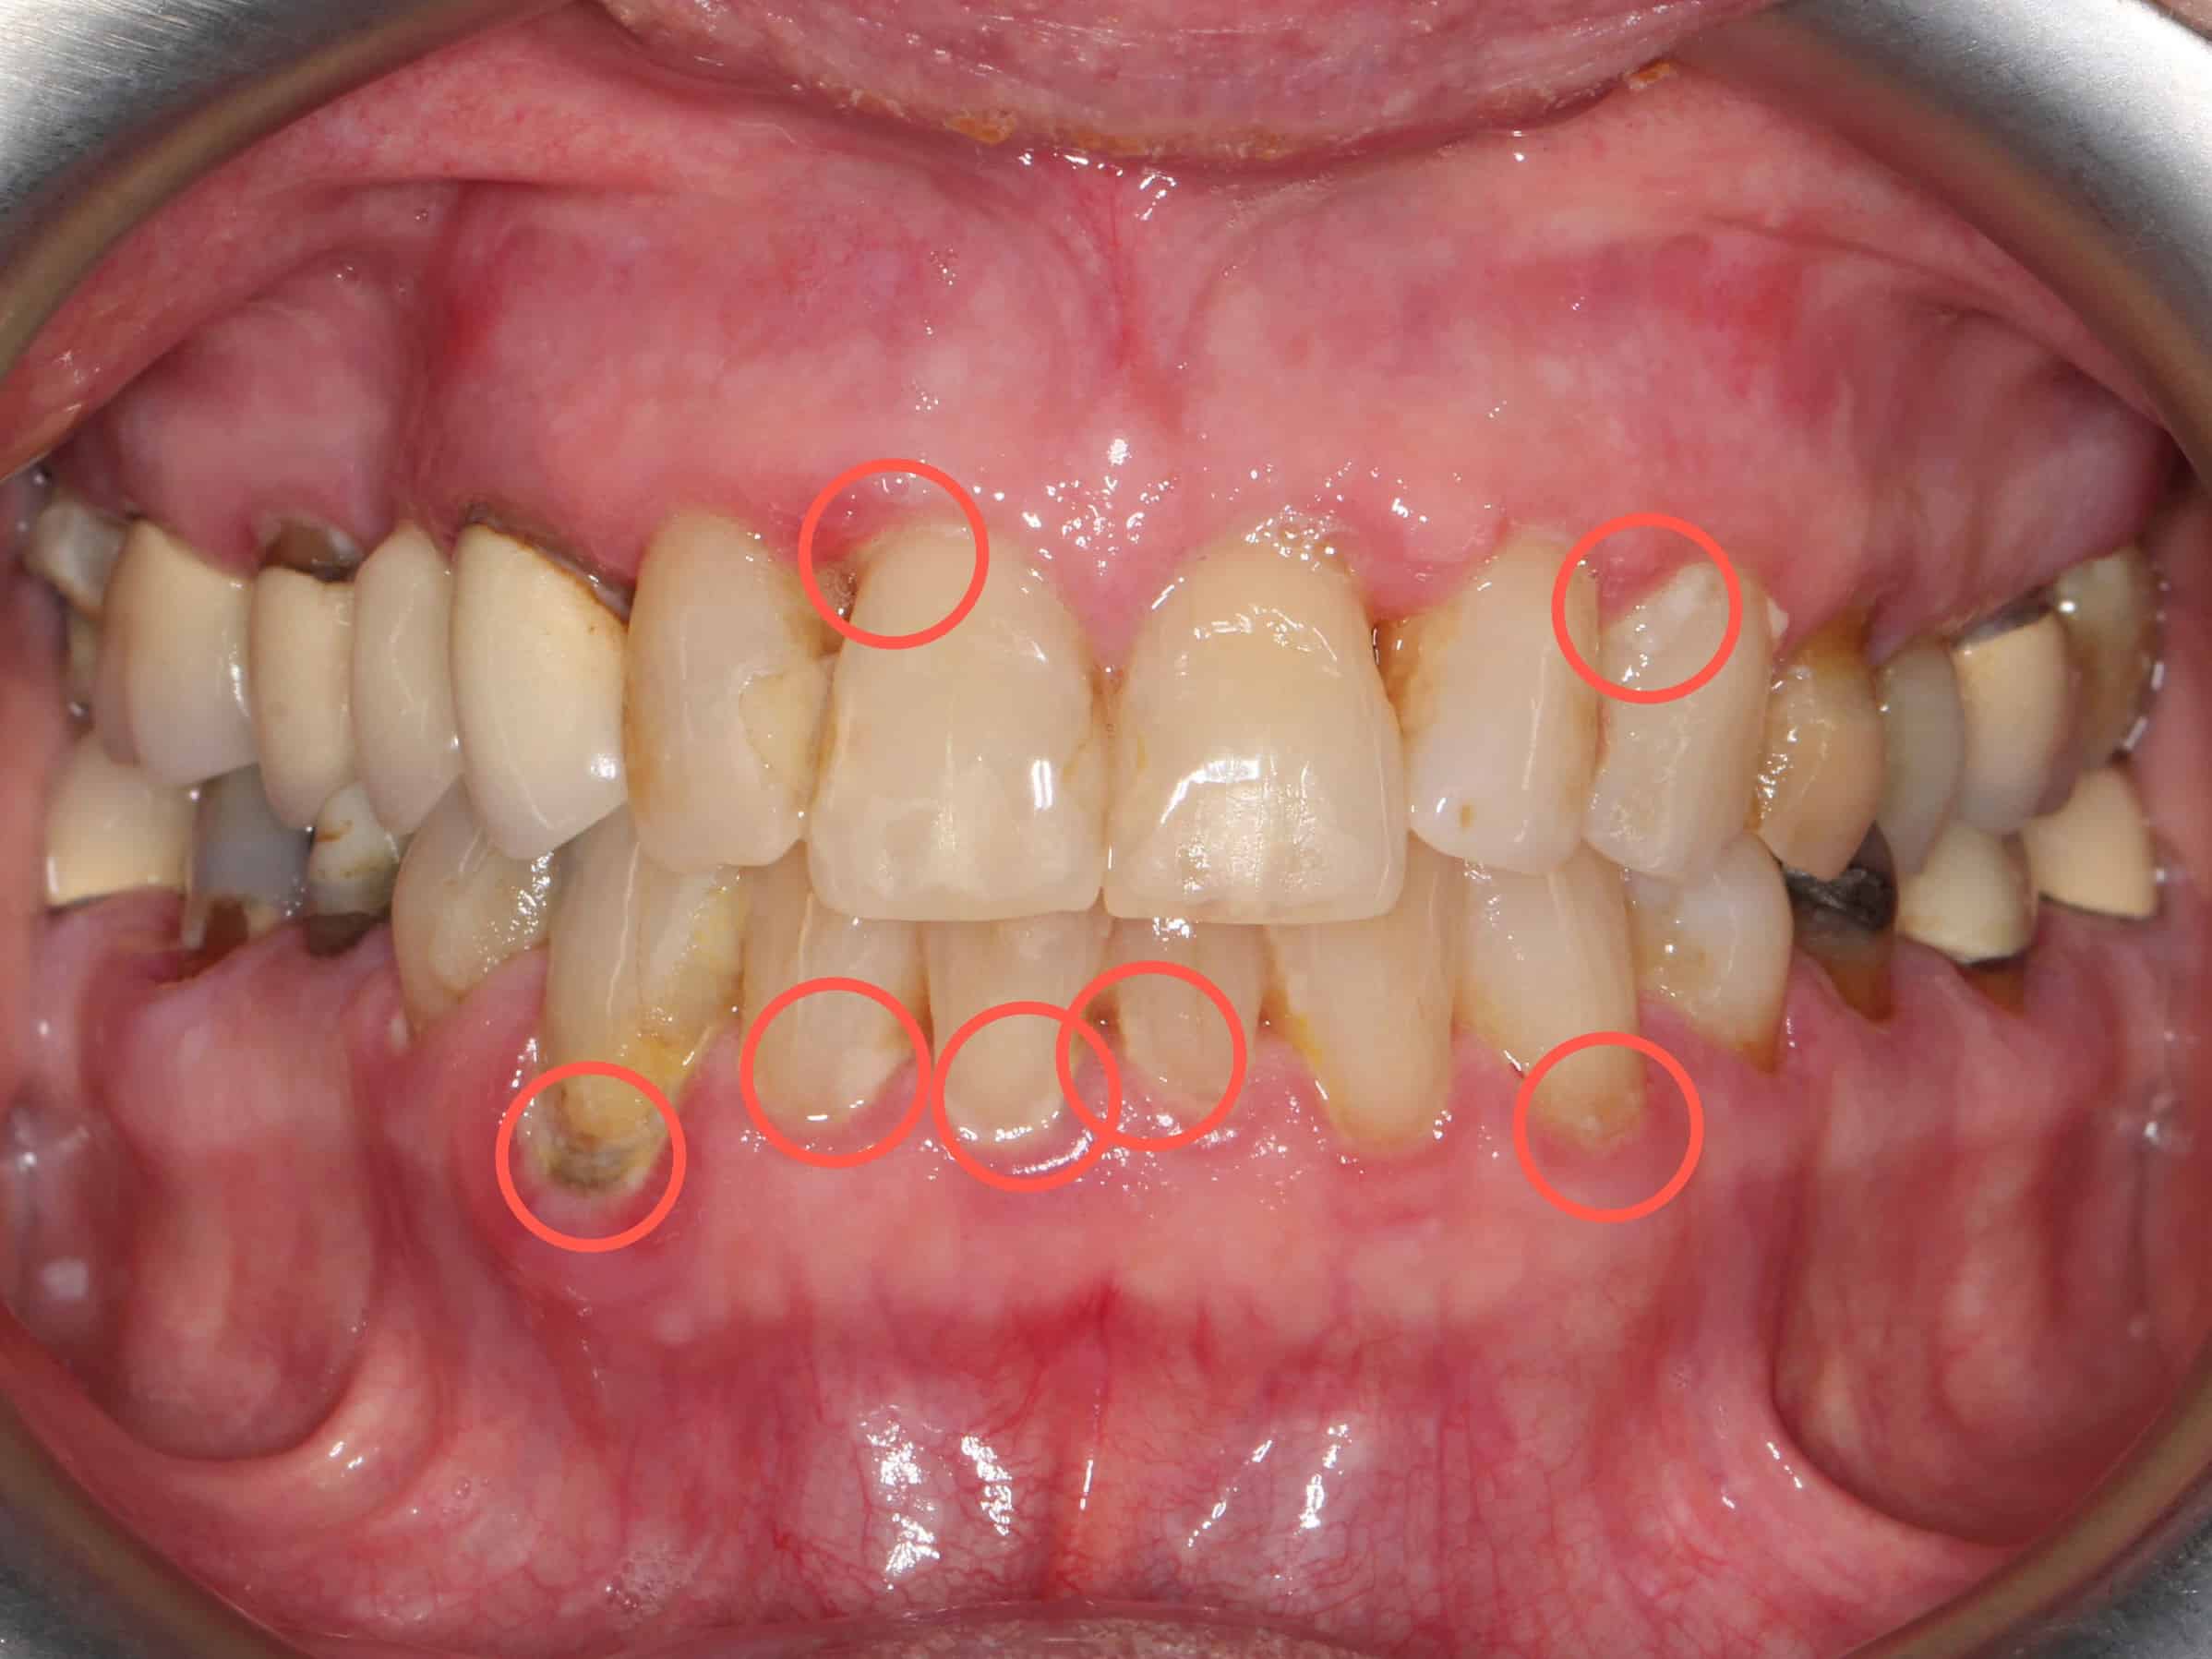

Før- og etterbilder